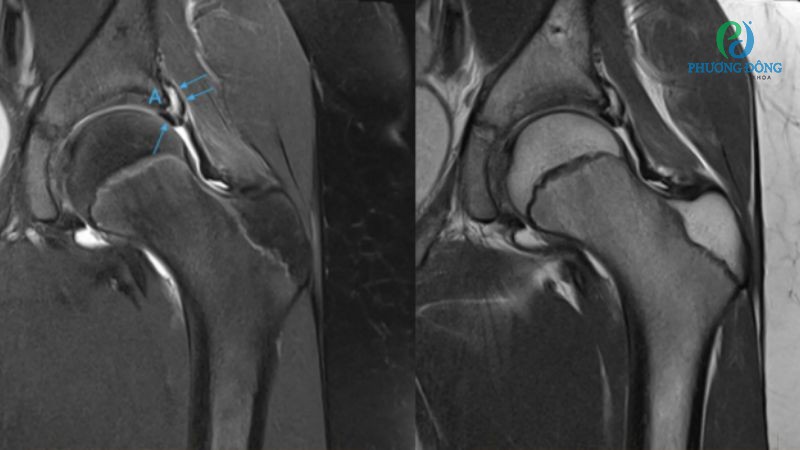

Rách sụn viền ổ cối

Sụn viền ổ cối có nhiệm vụ duy trì sự ổn định của khớp háng, tuy nhiên vị trí này cũng rất dễ bị rách do chấn thương hoặc vận động mạnh. Khi này bệnh nhân cảm nhận được rõ rệt cơn đau nhức sâu bên trong khớp, nghe được tiếng lạo xạo trong lúc di chuyển. Nếu không can thiệp sớm có thể gây đau kéo dài, hạn chế phạm vi chuyển động của khớp.

- Chẩn đoán hình ảnh với X-quang, MRI, CT-Scan giúp phát hiện sớm tổn thương về gãy xương, thoái hóa, rách sụn viền hoặc viêm bao hoạt dịch. Đặc biệt với trường hợp nghi ngờ chấn thương phần mềm như gân, dây chằng, thần kinh, bác sĩ sẽ chỉ định chụp MRI.